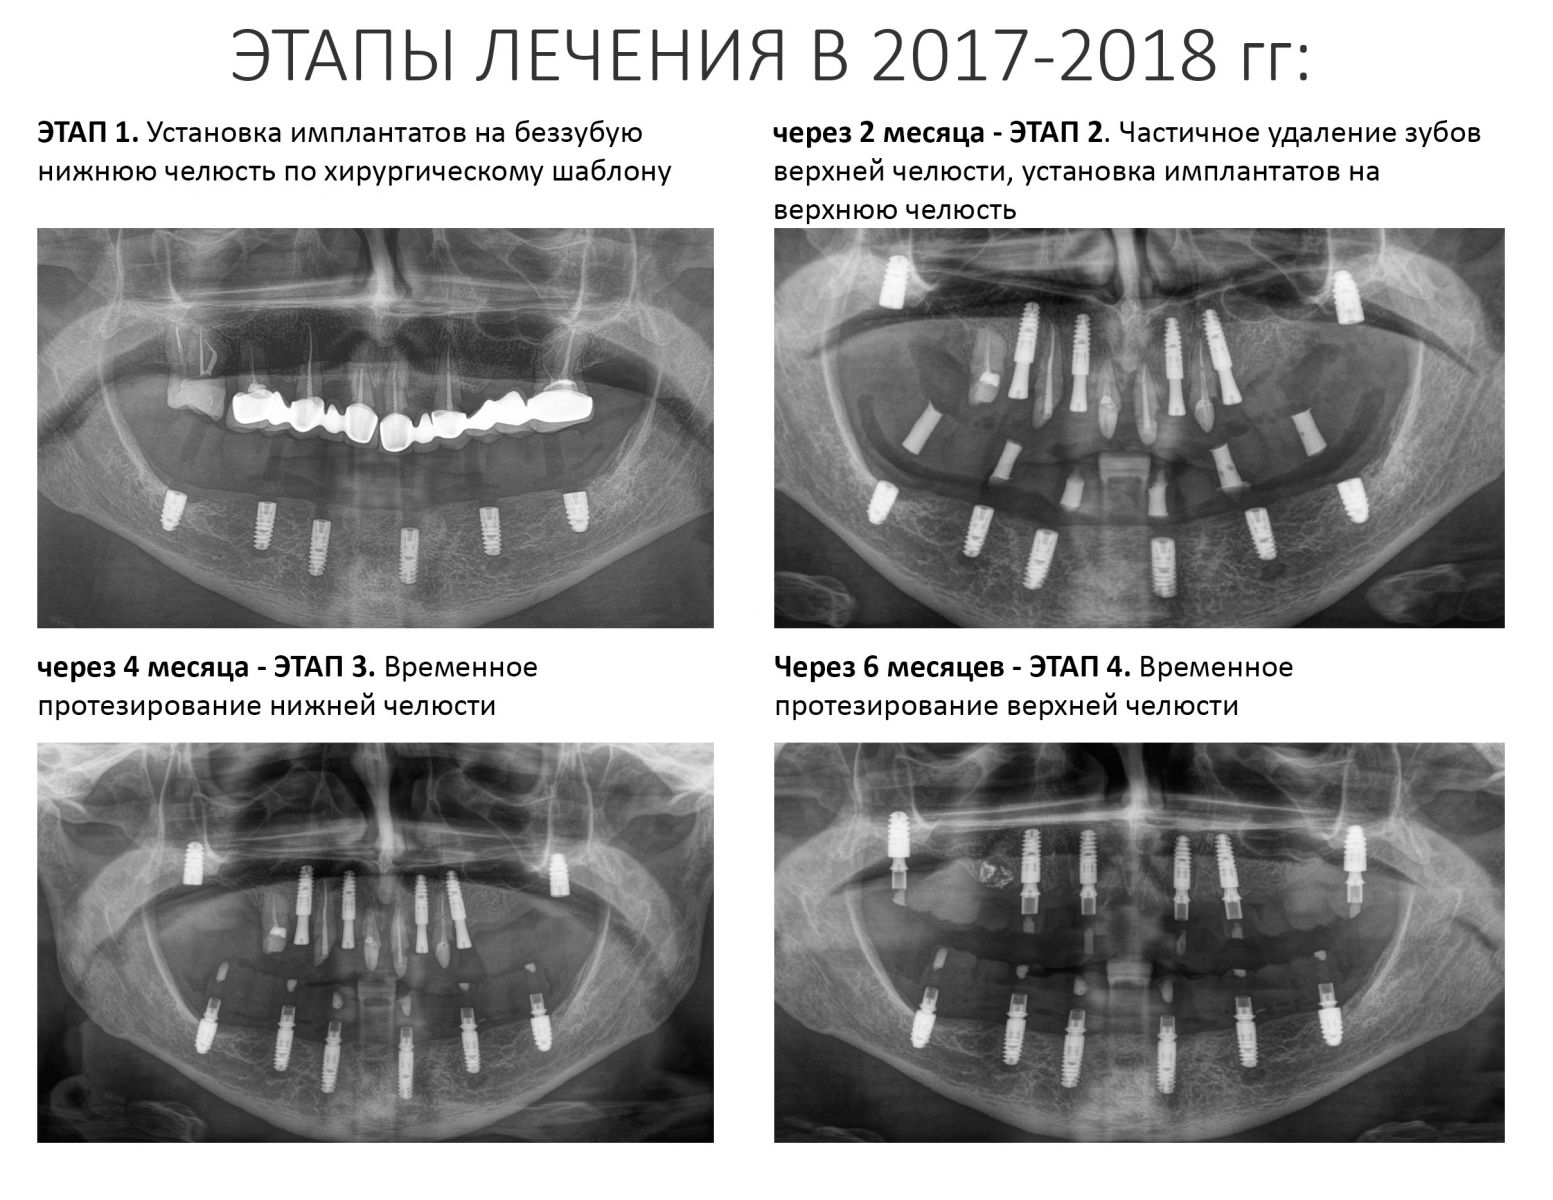

Пациентка того же возраста, что и Елена, начала лечение в нашей клинике около шести лет назад. В течение 2017-2018 гг. мы провели очень большую работу: